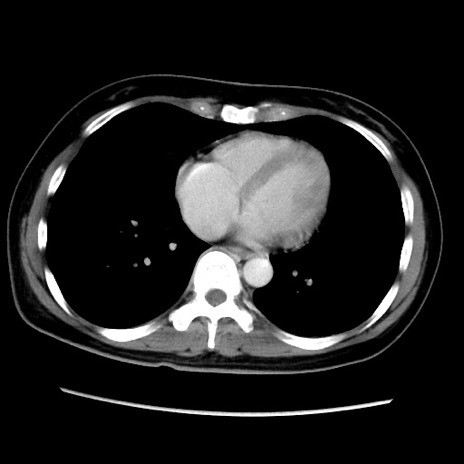

症例39(横断像)

【症例】40歳代女性

【主訴】上下腹部痛

【現病歴】2日目から下腹部痛あり。夜間は痛みで眠れなかった。昨日より上腹部痛と下痢が出現。臥位で痛みは軽快したため、休んでいた。本日になって臥位でも立位でも痛みが強くなってきたため救急要請。

【既往歴】子宮内膜症

【身体所見】部:平坦・軟、左上下腹部に圧痛あり、反跳痛あり。

【データ】WBC 21800、CRP 26.78